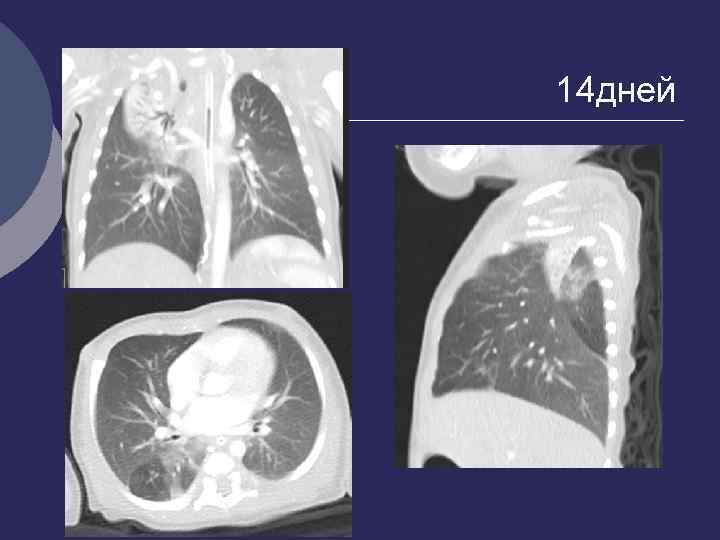

14 дней